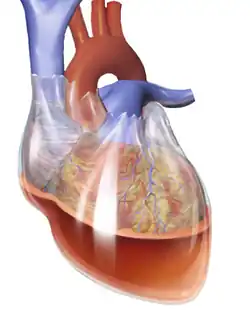

The pericardium, the double-walled sac surrounding the heart, consists of a fibrous pericardium layer on the outside and a double-layered serous pericardium on the inside.[18] Between the two layers of the serous pericardium is the pericardial space, which is filled with lubricating serous fluid that prevents friction as the heart contracts.[19] The outer layer of the heart is made of fibrous tissue[20] which does not easily stretch, so once excess fluid begins to enter the pericardial space, pressure starts to increase.[12] Consequently, the heart becomes compressed due to its inability to fully relax.[21]

If fluid continues to accumulate, each successive diastolic period leads to less blood entering the ventricles. Eventually, increasing pressure on the heart forces the septum to bend in towards the left ventricle, leading to a decrease in stroke volume.[12] This causes the development of obstructive shock, which if left untreated may lead to cardiac arrest (often presenting as pulseless electrical activity).[22] The decrease in stroke volume can also ultimately lead to a decrease in cardiac output, which could be signaled by tachycardia and hypotension.[21]

Tamponade can often be diagnosed radiographically. Echocardiography, which is the diagnostic test of choice, often demonstrates an enlarged pericardium or collapsed ventricles. A large cardiac tamponade will show as an enlarged globular-shaped heart on chest x-ray. During inspiration, the negative pressure in the thoracic cavity will cause increased pressure into the right ventricle. This increased pressure in the right ventricle will cause the interventricular septum to bulge towards the left ventricle, leading to decreased filling of the left ventricle. At the same time, right ventricle volume is markedly diminished and sometimes it can collapse.[15]